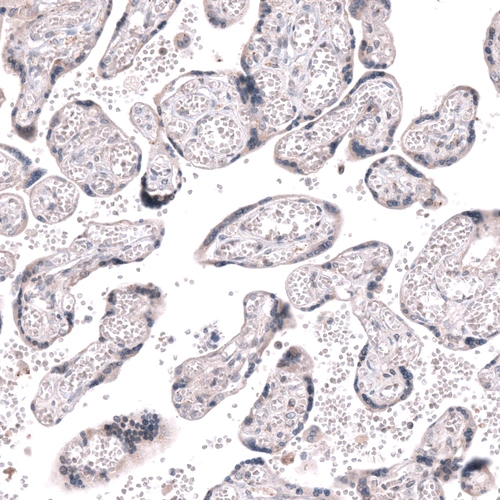

Immunohistochemical staining of human cerebral cortex shows strong nuclear positivity in oligodendrocytes.